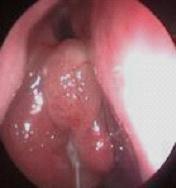

鼻炎长期得不到有效治疗导致鼻息肉以及鼻腔囊肿

经常鼻塞、流脓鼻涕、头痛多为鼻窦炎、鼻息肉等。除了流鼻涕外,长期伴有头疼症状。是早晨疼还是夜间疼?怎么减轻症状?在线咨询为你解答。